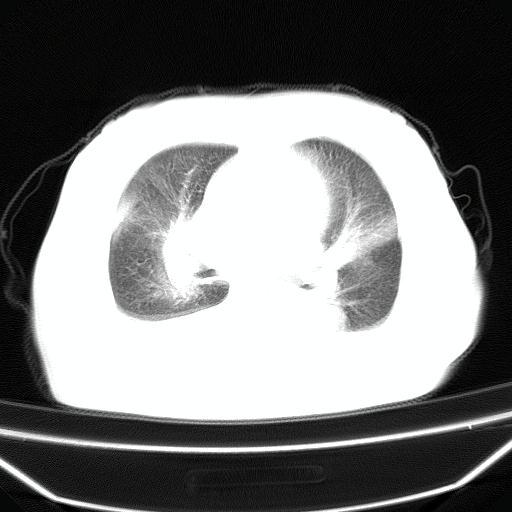

以下是引用liuyue在2008-4-19 22:25:00的发言:[br]先考虑:1.心衰伴肺水肿、双侧胸腔积液、叶间积液、双下肺不完全性肺不张; [br] 2.冠状动脉粥样硬化。

以下是引用jiangjing在2008-4-20 10:43:00的发言:[br]结合病史支持 冠心病[冠状动脉钙化],心功能不全,肺淤血、肺水肿,双侧胸腔与斜裂积液